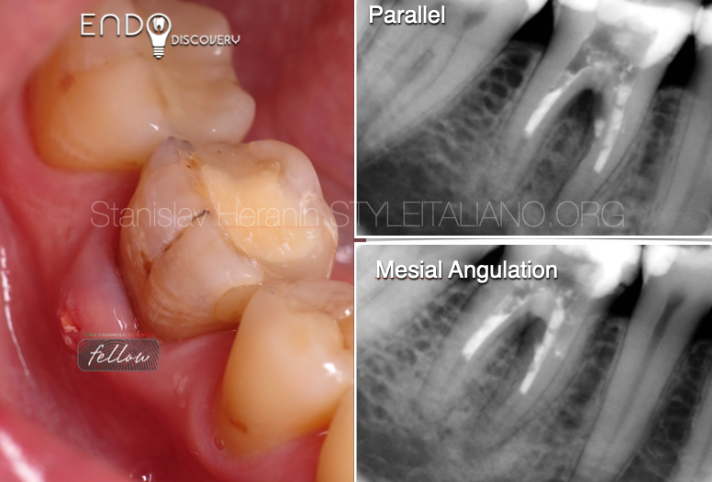

患者自述既往有多次根管治疗史。46牙存在旧的MOD复合树脂充填体破损。颊侧可见瘘管。诊断性X线片显示46牙根尖及根分叉区域透射影(怀疑穿孔)。叩诊无痛,牙周探诊在正常范围内。治疗计划为使用MTA进行非手术根管再治疗并修复穿孔。

根管充填:MB/L根管采用连续波加压充填

X线片检查

远中根管:MTA封闭